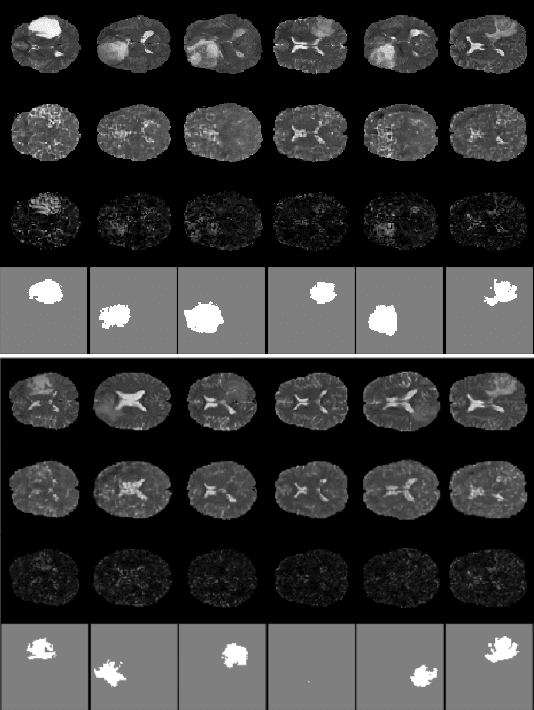

Abstract:Anomaly detection for Magnetic Resonance Images (MRIs) can be solved with unsupervised methods by learning the distribution of healthy images and identifying anomalies as outliers. In presence of an additional dataset of unlabelled data containing also anomalies, the task can be framed as a semi-supervised task with negative and unlabelled sample points. Recently, in Albu et al., 2020, we have proposed a slice-wise semi-supervised method for tumour detection based on the computation of a dissimilarity function in the latent space of a Variational AutoEncoder, trained on unlabelled data. The dissimilarity is computed between the encoding of the image and the encoding of its reconstruction obtained through a different autoencoder trained only on healthy images. In this paper we present novel and improved results for our method, obtained by training the Variational AutoEncoders on a subset of the HCP and BRATS-2018 datasets and testing on the remaining individuals. We show that by training the models on higher resolution images and by improving the quality of the reconstructions, we obtain results which are comparable with different baselines, which employ a single VAE trained on healthy individuals. As expected, the performance of our method increases with the size of the threshold used to determine the presence of an anomaly.